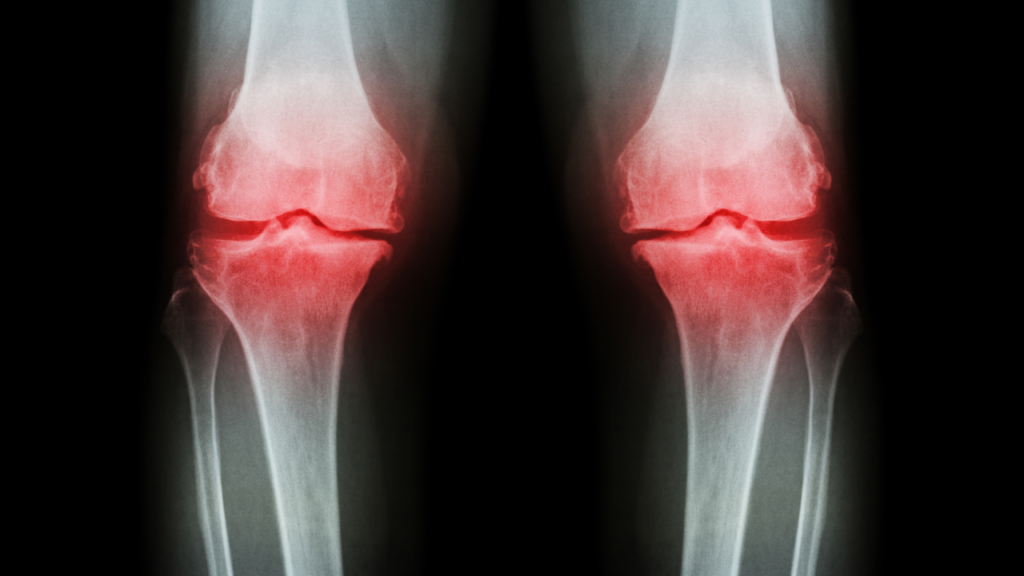

変形性膝関節症とは?

変形性膝関節症は、膝の関節軟骨がすり減ることにより、痛みや腫れ、動かしにくさを引き起こす病気です。現在では1000万人以上の方が膝の不調に悩まされており、特に女性に多く見られる疾患です。

症状の進行

- 初期症状:立ち上がりや歩き始めのときの痛み

- 中期以降:階段の昇り降りが困難になる、正座ができない

- 進行時:安静時でも膝の痛みや腫れを感じるようになる